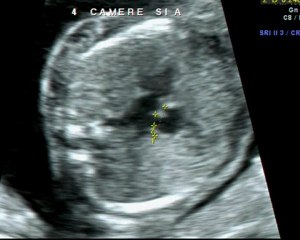

Difetto del setto atriale tipo ostium primum